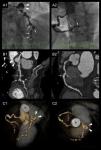

Coronary angiograms revealed a large aneurysm involving the origin of the circumflex artery, with a maximum diameter of 16mm, and irregular enhancement in the periphery with thrombus (Video 1 and Figure 1A1). The distal bed of the circumflex artery was very poorly perfused by collaterals of the right coronary artery. The left anterior descending artery also showed multiple saccular aneurysms and multilevel stenosis up to 70% with poor distal run-off (Videos 1 and 2 and Figure 1A1). The right coronary artery presented mild diffuse ectasia, multiple aneurysms and significant stenosis in the mid and distal portions (Video 3 and Figure 1A2). An aortogram with runoff showed a normal thoracic aorta.

Abnormal coronary artery appearance in different techniques. A large aneurysm (arrowheads) is seen at the distal edge of the left main trunk (A1, B1, C1 and C2). The left anterior descending artery (LAD) presents several aneurysms (arrows) but also severe stenotic lesions (resembling a string of beads) with a poor distal bed (A1, B1 and C1). Note the absence of circumflex artery visualization. The ectatic right coronary artery (RCA) also presenting aneurysmal formations (arrows) and obstructive lesions (A2, B2 and C2). A: coronary angiograms of the LAD and RCA. B: curved planar reformation (CPR) in multislice computed tomography (MSCT) of the LAD and RCA. C: Three-dimensional MSCT reconstructions (volume-rendering technique). *: ascending aorta.

Multislice computed tomography (MSCT) confirmed the appearance of the coronary arteries resembling a string of beads due to the presence of multiple aneurysms interspersed with critical stenotic lesions (Figure 1B and C). No other cardiac abnormalities were detected.